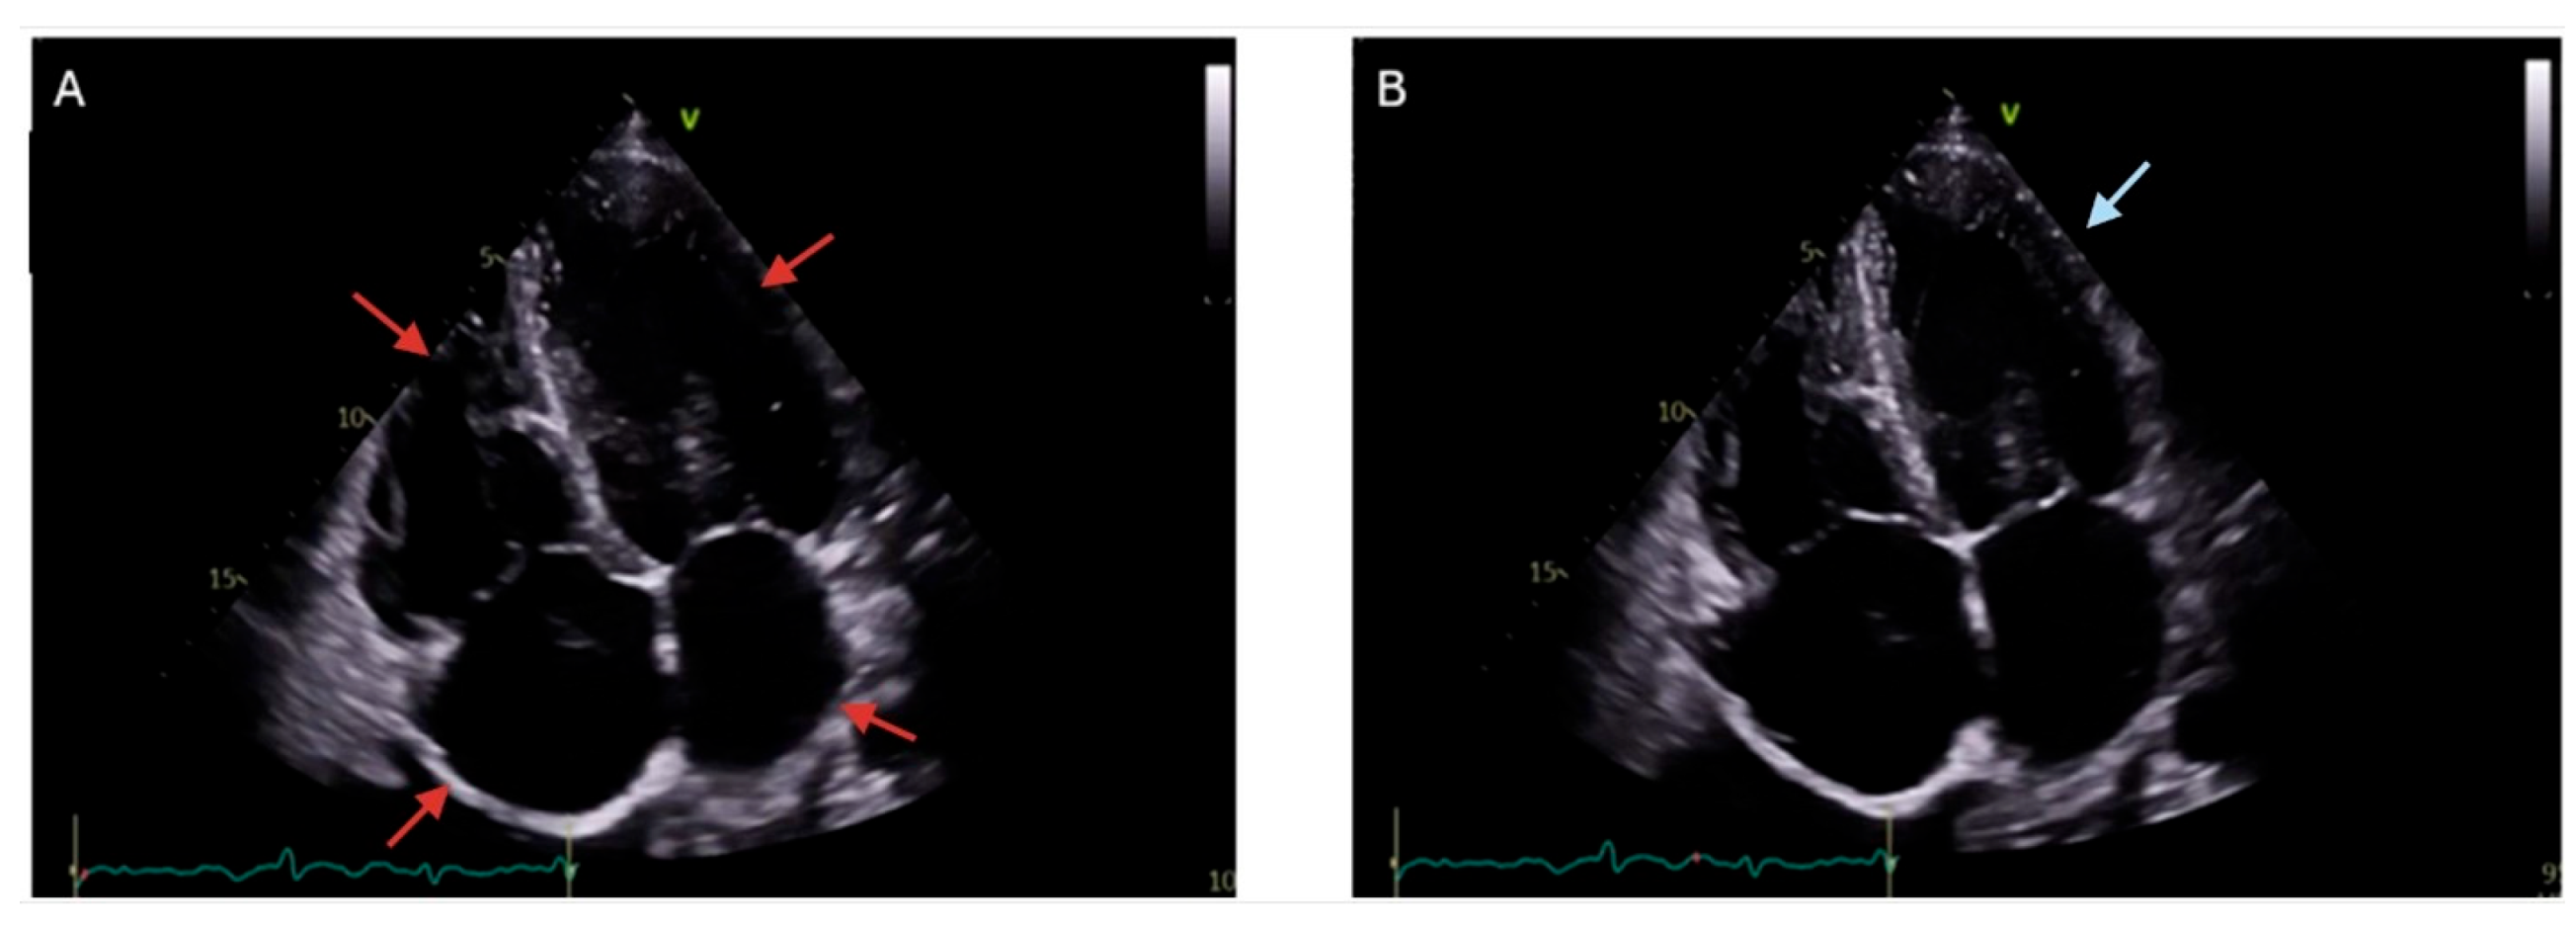

- Świątczak, M.; Rozwadowska, K.; Sikorska, K.; Młodziński, K.; Świątczak, A.; Raczak, G.; Daniłowicz-Szymanowicz, L. The Potential Impact of Hereditary Hemochromatosis on the Heart Considering the Disease Stage and Patient Age—The Role of Echocardiography. Front. Cardiovasc. Med. 2023, 10, 1202961. [Google Scholar] [CrossRef]

- Palka, P.; Macdonald, G.; Lange, A.; Burstow, D.J. The Role of Doppler Left Ventricular Filling Indexes and Doppler Tissue Echocardiography in the Assessment of Cardiac Involvement in Hereditary Hemochromatosis. J. Am. Soc. Echocardiogr. 2002, 15, 884–890. [Google Scholar] [CrossRef]

- Montvilaitė-Laurinavičienė, A.; Dirsienė, R.; Neverauskaitė-Piliponienė, G.; Banišauskaitė, A.; Šukys, M.; Šakalytė, G.; Ereminienė, E. Heart Failure of Very Rare Aetiology—Haemochromatosis Type 3: A Case Report. Eur. Heart J. Case Rep. 2024, 8, ytae637. [Google Scholar] [CrossRef]